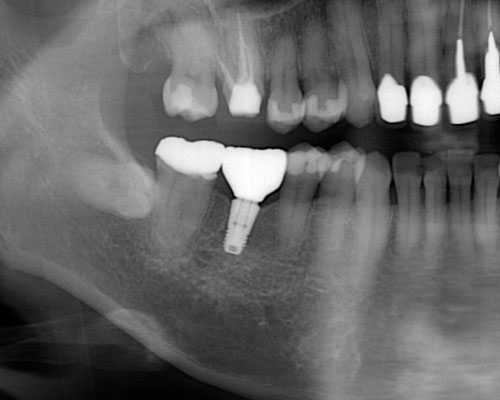

みなさんは歯を失ったら、元のように「噛めるようになりたい。」と考えられるのではないでしょうか。そして3つの選択肢のうち、ブリッジとインプラントは元の歯と同じように噛めますが、入れ歯は3割から5割の力でしか噛むことができませんので、多くの方がブリッジかインプラントのどちらにするかと悩み始めます。歯にダメージを与えないインプラントの方が良いに決まっていますが、「骨に金属のビスを打ち込む」ということに抵抗を感じる方も多いと思います。

しかし、ここで多くの方が見落としているポイントがあります。ブリッジや入れ歯を入れても、歯の根が増えるわけではないので、残っている歯の負担を軽減することはできません。これが、インプラントなら新たな支えとなるため、残っている歯の寿命を縮めることはなくなることです。

インプラントを入れるには割り切って考えることが必要です。インプラントは完全なものではありません。天然歯に比べて多くのリスクを抱えています。しかし、たとえ10年しかインプラントが保たなかったとしても、その10年間はインプラントが噛む力を負担して、他の歯にかかる力を軽減し、歯の寿命を延ばしてくれたと評価することができれば、インプラントを入れた意味は十分にあると思います。